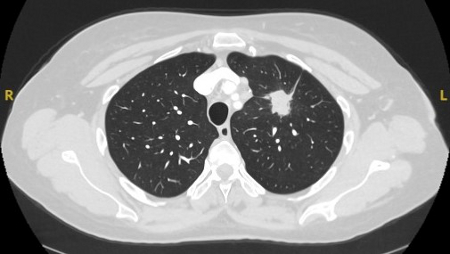

A dense central, laminated, chondroid pattern of calcification (often called popcorn calcification) or a diffuse pattern of calcification strongly suggests that a nodule is benign.[Figure caption and citation for the preceding image starts]: Computed tomography (CT) showing a benign calcified granuloma in the right middle lobe, stable >10 years. The patient reported previous pneumonia on the same sideFrom the collection of Dr George Tsaknis, MD, PhD, FRCP(London), MRQA, MAcadMEd, PGCert; used with permission [Citation ends].